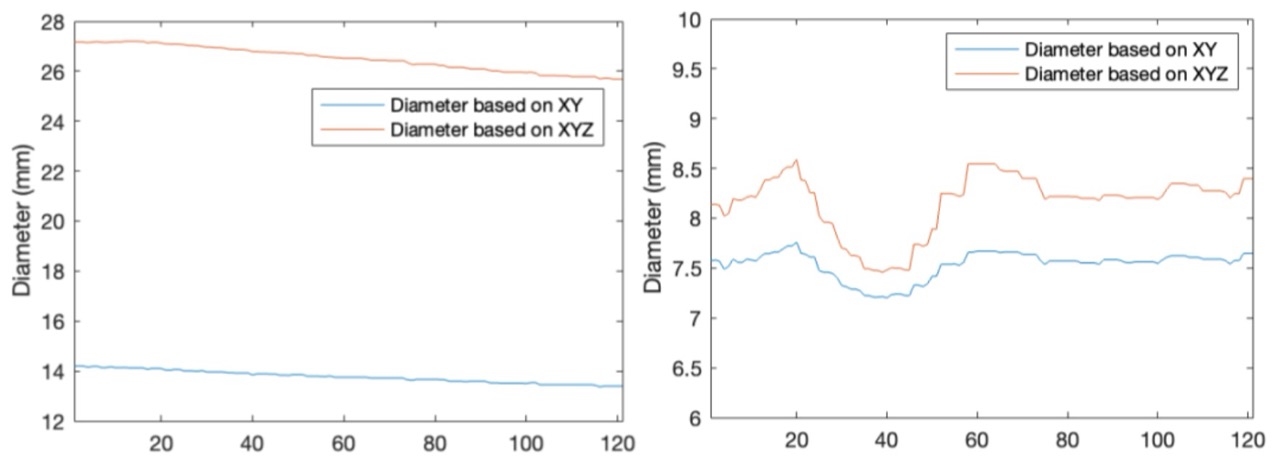

- Disparity Mapping & Depth Recovery: Generated a dense disparity map and back-projected image points to compute real-world 3D coordinates.

- Quantitative Tool Analysis: Estimated the physical diameter of a surgical tool (∼7.53 mm) directly from the reconstructed point cloud using geometric analysis, achieving 95% accuracy.

✅ Demonstrated the full stereo vision pipeline from calibrated image pairs to quantitative 3D metric extraction in a surgical context — achieving 95% accuracy in depth estimation.